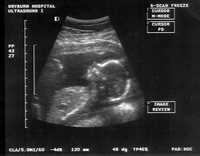

Abortion opponents said the bill by Sen. Dan Patrick, R-Houston, which would force doctors to perform the sonograms and check a heartbeat monitor at least two hours before the abortion, will remind women that they're considering terminating a human life. They say it still gives women a choice: the bill, as it's currently written, lets them to decide whether to see the image or listen to the heartbeat.

And women opposed to abortion held their own news conference, where a woman who was eight weeks pregnant was hooked up to a sonogram and a video of her fetus was projected onto a screen.